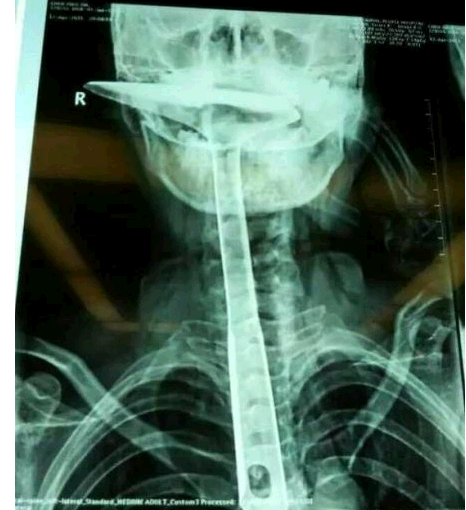

炒菜用的锅铲,长达30公分,活生生插进自己的食道,只剩下铲勺露在嘴巴外面,整个食道严重受损。医生都不禁感叹:“这真的是50年难遇的病例。”

陈女士被紧急送到东莞第五人民医院,医生拍片显示,整个铁锅铲把手已经在胸里了,病情严重。当晚,陈女士就被转到了康华医院。“患者来院时,嘴巴里只剩一个锅铲铲勺露在外面,整个锅铲手柄已经被插入到食道里了。”康华医院胸外科接诊医生陈羽彪说,检查发现,锅铲总长大概30公分长,手柄直径约2.5公分,整个已经插入食道,食道表皮粘膜损伤严重,且被捅破了一个洞,“而且,手柄已严重挤压到了肺部,导致右肺部已无法正常扩张。”

“这样的病例,不说100年难遇,也是50年难遇了。”康华医院胸外科主任肖朴说,患者情况严重,医院立即组织专家会诊。“胸腔全是大血管,一旦拔出就有可能大出血,危及性命。”当天晚上11点,医生决定为患者进行一期手术即食道扩置手术,“我们先将锅铲从食道里面拔出来,由于胸位食道受损严重,只能切除了。”

医生介绍,食道总长约25公分,患者切除了20公分,切除部分主要集中在胸位段,食道只保留到了颈部,只能露出来进行医学处理,吞咽口水、积液进行人工及时清理更换。”